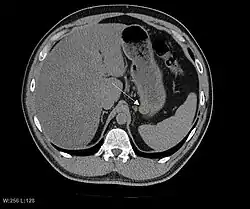

Tomografia komputerowa (TK) pełni rolę w rozpoznaniu choroby, ocenie jej zaawansowania oraz planowaniu postępowania chirurgicznego[47][2][5][44]. W tomografii komputerowej GIST jest obrazowany jako dobrze odgraniczona zmiana poza światłem przewodu pokarmowego[2]. Gęstość zmian jest różna, zmiana może ulegać niejednolitemu wzmocnieniu kontrastowemu[5], co jest szczególnie zaznaczone przy większych guzach z obecną martwicą i obszarami krwotocznymi[2]. Typowo obraz jednorodnego wzmocnienia kontrastowego przemawia za łagodnym charakterem zmiany[10]. Tomografia komputerowa jest przydatna w rozpoznawaniu przerzutów odległych, szczególnie do wątroby[2]. Rezonans magnetyczny (RM) jest przydatny w ocenie zmian zlokalizowanych w miednicy oraz oceny rozsiewu do otrzewnej[2].